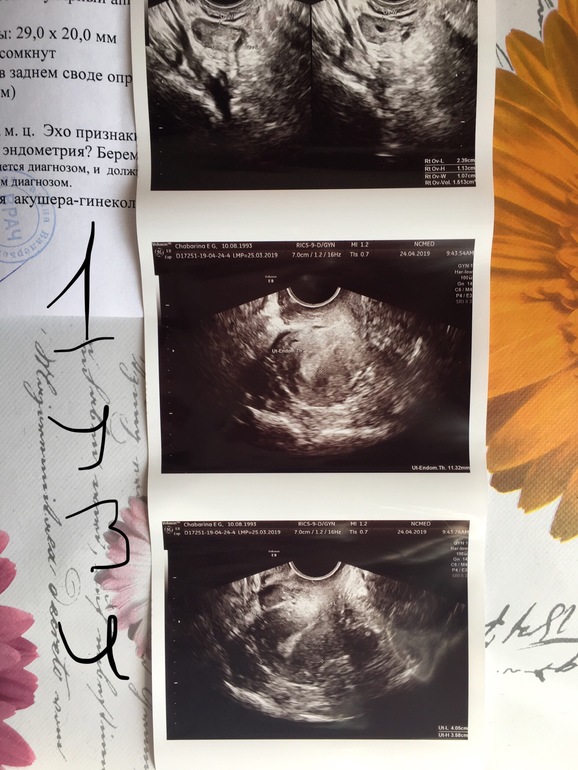

Вопросы про УЗИ, обследования и анализы: что, где, как, когда?Добрый день , я у вас новенькая ) задержка 2 недели , на первой недели была на узи и сейчас . При первом ставили маточную, сейчас внематочную . Помогите разобраться 🙏🏻😩 фото под катом .

К сожалению... 90% - внематочная... так как при ней очень часто бывает ложное плодное яйцо в матке.. у меня именно так и было. 1.9 мм - «пя» и через неделю на узи внематочная в левой трубе

Я думаю, что надо в больницу,,там врачи пусть еще раз все проверят, и принимают решение. Судя по узи, очень похоже на вб.

Вот на втором узи написано что что то около яичника 21 мм , разве мог так вырасти ?